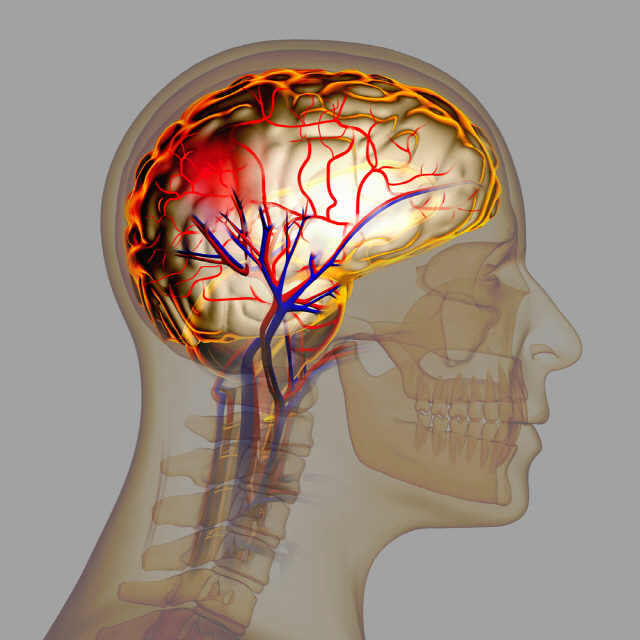

뇌출혈 원인

고혈압은 뇌출혈의 가장 큰 원인으로 볼 수 있는데 고혈압 환자라면 혈압이 갑작스럽게 상승하는데 이 때 산소와 영양소가 뇌로 들어가는 통로인 혈관에 변화를 일으키는데 혈관이 버티지 못하고 터지게 됩니다. 뇌동정맥의 기형에 의한 뇌출혈, 뇌동맥류 파열에 의하여 나타나며 잦은 흡연이나 다른 질병의 합병증으로 인해 발생할 수 있으며 뇌손상은 팔, 다리, 심하면 얼굴등 신체 일부분이 평생 마비시키며, 골든타임을 놓칠 경우 사망할 수도 있어 뇌출혈 전조증상에 대해 알고 있는 것이 좋습니다.